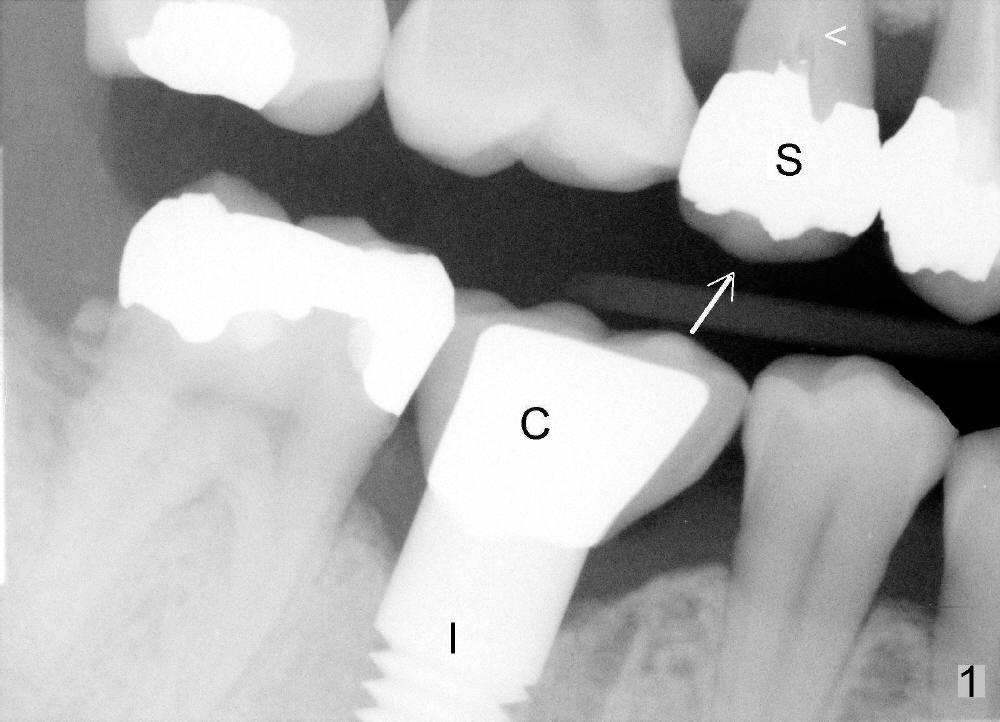

A few months after cementation of implant (Fig.1 I) crown (C) at #30, a 44-year-old man fractured the tooth #4 with MOD amalgam (S) and root canal thereapy (<) while he was visiting his home country. Fig.2 shows the socket (black arrowheads) and bony defect (white arrowheads).

Osteotomes are used to form initial osteotomy, approximately 11 mm deep, 4 mm wide. Bicon reamers (Fig.3 R) are used to increase osteotomy while collecting autogenous bone; it appears that the sinus floor is partially penetrated (dashed line). After sinus lift (Fig.4 dashed line), a 5x14 mm cylindrical tissue-level implant is placed (I; arrowheads: sinus floor). There is no intraop nasal hemorrhage. Amoxicillin is prescribed postop (500 mg tid for 7 days). There is purulent, particulate discharge from the right nostril postop. One month later, the implant is loose and removed.

Four months after implant removal, the bony defect appears to increase (Fig.5). Reamers (Fig.6 R)and osteotome (Fig.7 O) are short of the sinus floor (arrowheads). A 5x14 mm tapered implant is placed with primary stability (Fig.8 I). The implant is placed ~ 2 mm deeper (Fig.9). No bone graft is used for sinus lift. There is no complication. The sinus floor appears to be repaired 4.5 months postop (Fig.10). Fig.11 (trimmed from panoramic X-ray) is taken 1 year 7 months post cementation. The bone remains stable 4 years 2 months post cementation (Fig.12); the mesial defect is most likely related to extraction trauma (*).